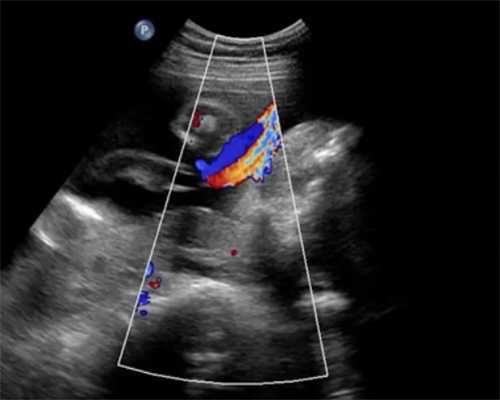

纵隔子宫属于先天性子宫发育畸形,通常对性生活无直接影响。但若伴有阴道纵隔,同房时可能会产生疼痛感。在辅助生殖术前检查中,若发现纵隔导致了反复流产或不孕,则需进行宫腔镜手术。若妇科阴道镜显示阴道同样存在发育畸形,可配合进行阴道整形手术,以改善生活质量及后续受孕条件。